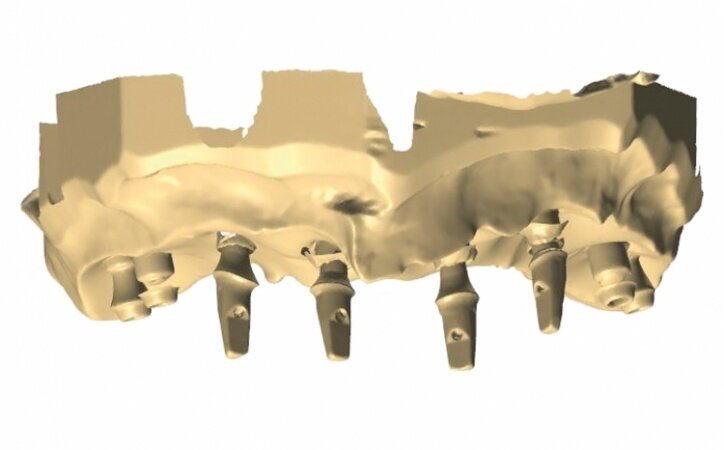

In the next phase, implants were inserted. In compliance with the results of the CBCT study, a sinus lift procedure was performed with a simultaneous implantation in the region of lateral teeth. Eight Ankylos implants were introduced, raising both maxillary sinuses at the same time. After six weeks, the implant exposure procedure was performed. Because of the fact that implants were partially anchored into the bone at the lateral section, partially within the augmentation material while primary stability was achieved, we decided to expose implants at lateral sections without occlusal load so as to perform the so-called bone training with a view to improving the condition of the bone being regenerated. An impression was taken (Figs. 7 & 8) for the positional model and for the preparation of the temporary prosthesis based on telescopes.

The model was scanned while the abutments were made ready in such a way that they could serve as telescopic crowns, also in the final stage (Fig. 9). Primary and secondary telescopic crowns were designed on the abutments (Figs. 10 & 11) on the assumption that secondary crowns had been made ready twice, that is, for the sake of temporary prosthesis and at the same time for gluing it into the final construction (Figs. 12 & 13). Abutments were mounted on implants by means of Pattern Resin (Figs. 14 & 15) in such a way that the position does not change during mounting.